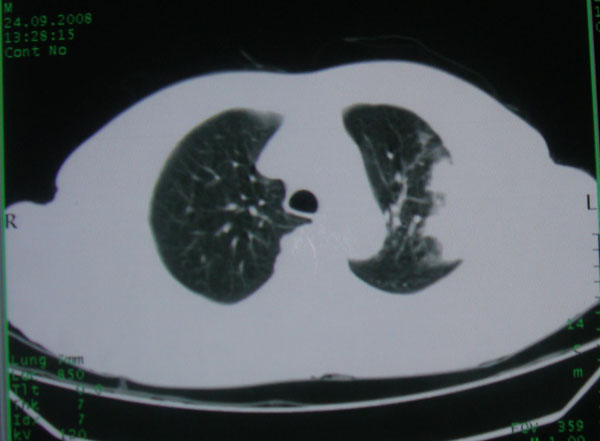

患者男性58岁因二周前起咳嗽,今天胸片示左上肺占位性病变行ct检查,无发热,无咯血痰.

左上肺感染性病变,结核伴空洞形成可能,左上肺膨胀不全

左肺上叶病灶,实变但见含气支气管、空洞但未见壁内结节及积液;

考虑:①感染性病变(包括特殊感染型肺tb)

②肿瘤性病变(考虑患者年龄比较大的关系/所以不排除)

初学者。。。左肺空洞性病变,并可见阻塞性肺不张改变,鉴于患者为老年男性,且临床症状仅有咳嗽,全身中毒症状不明显,所以我首先考虑为左肺癌性空洞并左侧肺门淋巴结转移伴左肺阻塞性肺不张。结核性空洞放于第二位考虑,可以进行相关实验室检查。希望能有病理结果,谢谢!!!!!

左肺上叶实变影,内见支气管充气征及空洞影,病人年龄较大,无发热及结核中毒症状,心影左移,未见纵隔淋巴结肿大;不知实验室检查结果如何?有否嗜酸细胞增多,有没有进行治疗?就目前资料首先考虑1.感染性病变,2.慢性嗜酸性肺炎?可结合实验室检查并短期治疗复查,肺癌不能排除。